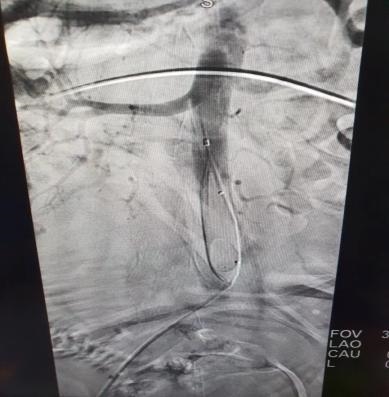

腹主动脉球囊阻断术

产科主任冉隆珍立即组织相关科室进行讨论,为降低患者大出血风险,最大限度保留产妇子宫,保障母婴安全,决定为该患者实施腹主动脉球囊阻断术辅助剖宫产术。在征得患者家属同意后,4月26日,由妇产科主任冉隆珍主刀,副主任蔡蓉、主治医师熊英协助,介入中心、麻醉科、手术室、新生儿科等科室密切配合,为患者实施腹主动球囊阻断术辅助剖宫产术。术中产妇子宫前壁与腹膜及膀胱广泛致密粘连,胎盘位于子宫前壁,植入子宫肌层,部分达子宫浆膜层。胎头娩出后,立即应用压力泵充盈球囊阻断腹主动脉,娩出胎盘及缝合修补胎盘附着面,手术出血明显减少,全程历时1小时30分钟。术后,在产科全体医护人员的精心治疗和悉心护理下,母子平安,于近日顺利出院。